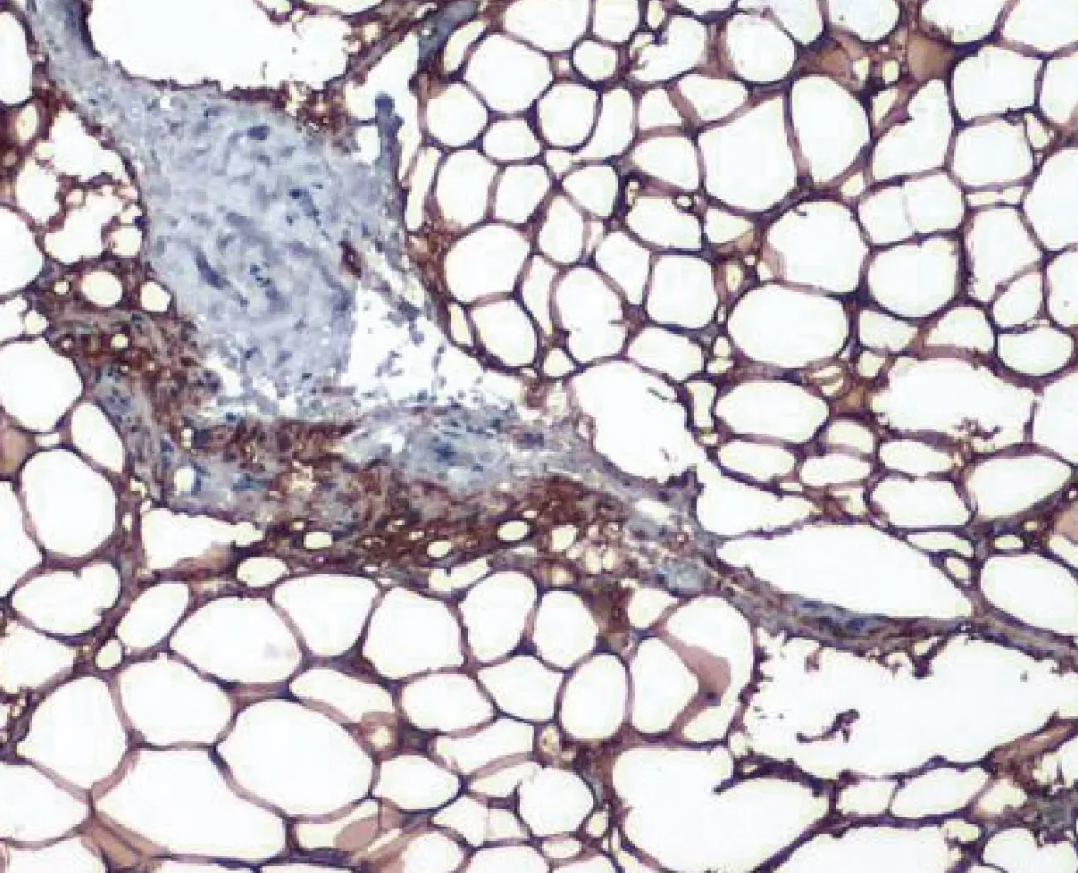

肥胖症的特征是脂肪中的脂质累积增加,导致肥胖组织肥大、脂解作用受损以及其他组织中异位脂肪沉积,并与促炎性表型相关的脂肪功能紊乱有关,脂肪组织是一种生物热量储存库,当营养过剩时,脂肪膨胀以储存脂质,并因应能量不足而释放脂质(脂肪变小)。脂肪细胞(adipocyte)为脂肪组织的主要细胞类型,并负责将多余的热量以甘油三酸脂(triglyceride)的形式储存在它们的细胞脂质滴中,防止异位脂质沉积和其他细胞的脂毒性,脂滴里的甘油三酸脂越多,脂肪细胞体积越大,之后就会变成肥胖了。脂肪细胞以多种亚型存在,以颜色区分为白色至棕色,白色脂肪细胞构成典型的脂肪细胞,代表内脏和皮下脂肪储存库中的大多数细胞,这些储库因肥胖而扩展,在能量稳态控制中起主要作用,不仅充当能量储存和利用的储存库,而且还感知能量需求并分泌旁泌因子来调节其他代谢组织,例如: 在高能量状态下,脂肪细胞分泌瘦素(leptin),从而集中减少食物摄入并增加能量消耗。棕色脂肪细胞包含较小的棕色脂防储库,在大多数哺乳动物物种地发热中起作用 (2)。 |

| 图一: 肥胖中的脂肪细胞 |